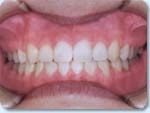

上の前歯が深くかぶさり下の前歯が見えません。

意外に知られていない不正咬合ですが、上の歯が深くかぶさって、下の歯がほとんど見えない状態です(A1)。

治療後は前歯のかぶり具合は正常になり(B1)、上下の歯列もきれいなアーチ(円弧)をえがいています(B2,B3)。